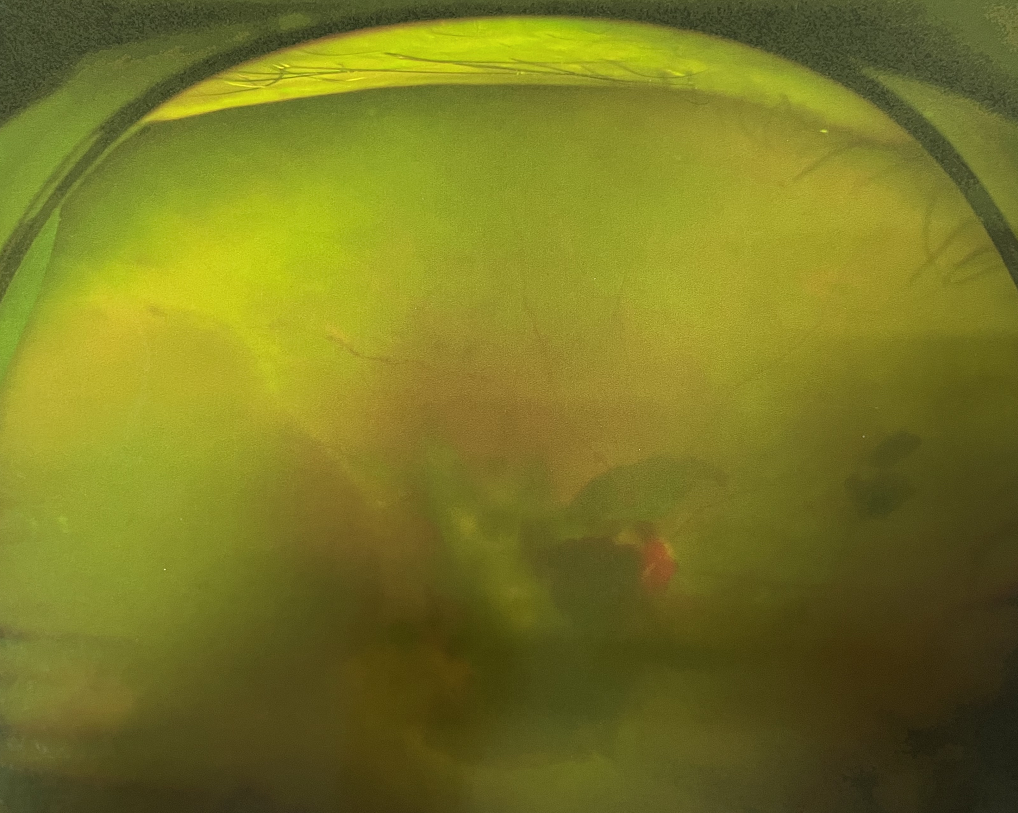

糖尿病視網(wǎng)膜病變是糖尿病在眼部的主要并發(fā)癥,是我國四大致盲眼病之一,主要以視網(wǎng)膜血管改變?yōu)椴±硖卣?。眼底多表現(xiàn)為視網(wǎng)膜出血、滲出、新生血管及增殖膜形成,嚴(yán)重威脅患者的視覺健康。

糖尿病視網(wǎng)膜病變

糖尿病視網(wǎng)膜病變可分為六期:

Ⅰ期:有微血管瘤或并有小出血點(diǎn)。

Ⅱ期:有黃白色“硬性滲出”或并有出血斑。

Ⅲ期:有白色“軟性滲出”或并有出血斑。

?、羝冢貉鄣子行律芑虿⒂胁Aw積血。

?、跗冢貉鄣子行律芑虿⒂欣w維膜增生。

Ⅵ期:眼底有新生血管或并有纖維膜增生,并發(fā)視網(wǎng)膜脫離。